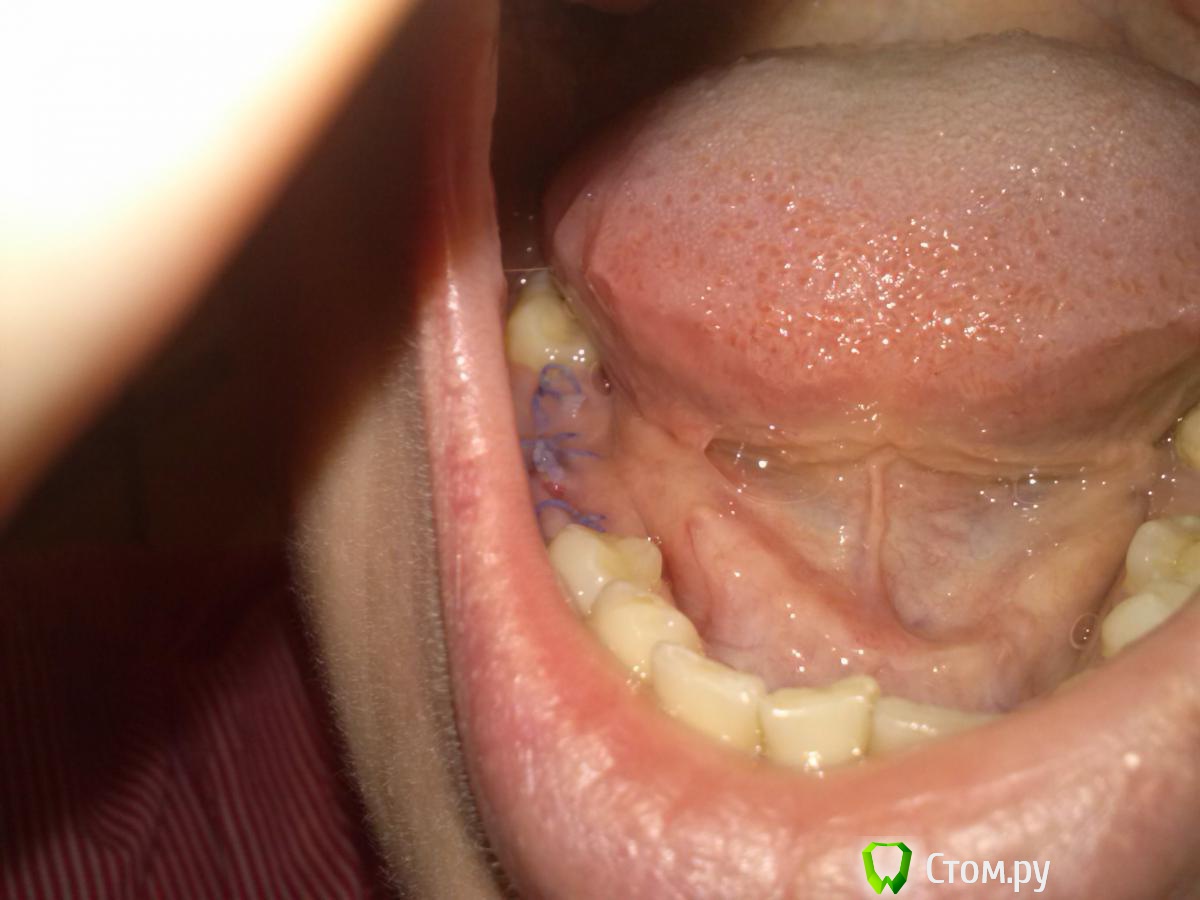

essliness Опубликовано 12 января, 2014 Поделиться Опубликовано 12 января, 2014 Добрый день, были удалены три зуба на нижней челюсти и наложены швы. Материал шва не знаю, снимать врач не говорил приходить. После удаления прошло 2,5 недели, швы неприятно пахнут, узелки отторглись и болтаются, залезая в ранку, доставляют дискомфорт при еде. Сделала фото - все в порядке с этими швами, снимать не надо? И как долго они тогда будут рассасываться? Заранее благодарю. Ссылка на комментарий